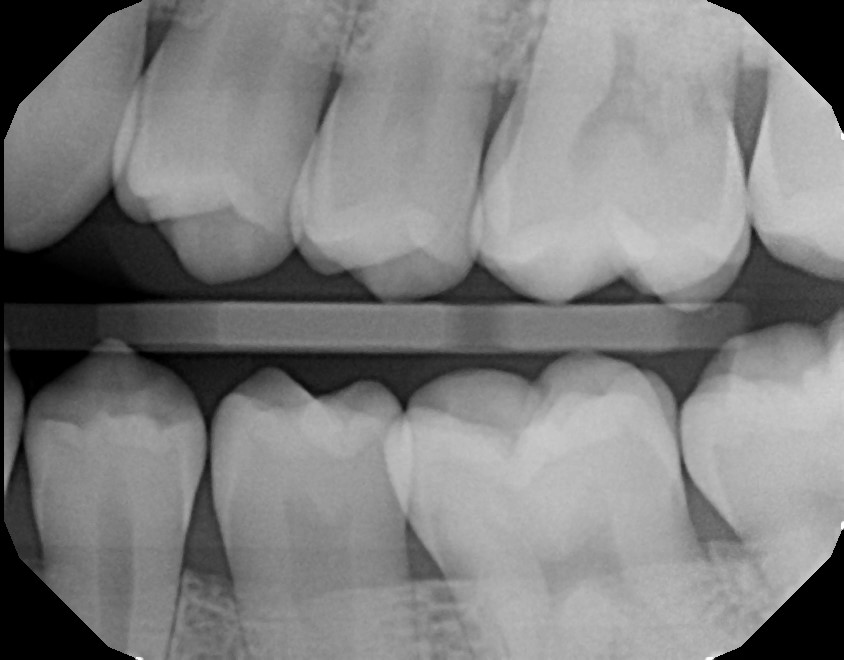

Teeth

Many people think that dental x-rays aren’t as exciting as those of other body parts. I don’t think that could be further from the tooth.

2022 June: Full Set

From Victoria Olshansky D.D.S. in West Hollywood.